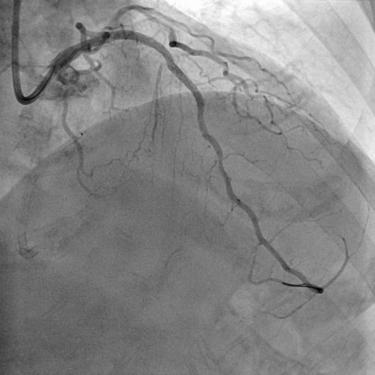

麻醉顺利,血管外科通道建立,ECMO成功运转,但困难如期而至。患者的左右血管都存在严重病变,其中右边是完全闭塞的,而且看不出堵塞的入口在哪里,进攻的导丝没有方向,这类病变处理的难度系数是最高的。罗裕主任凭借丰富的手术经验,利用不同导丝的触觉反馈,首先将微导管引导入冠脉结构,再换用不同硬度和不同塑形的导丝成功突破远端纤维帽,有惊无险的开通了右边血管。

左图术前右冠,右图术后右冠